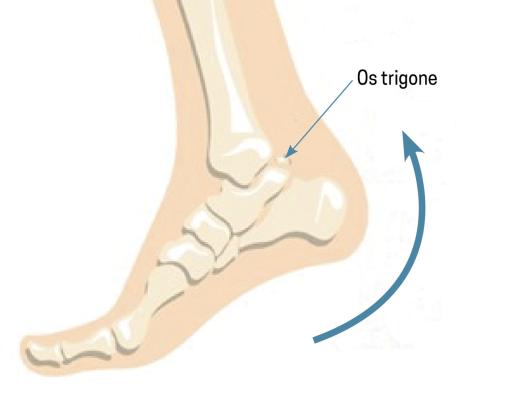

L’os trigone est un os dit surnuméraire situé derrière le talus (fig. 2). Il résulte de la non-fusion du versant postérieur du talus entre l’âge de 7 et 13 ans.1 Sa présence peut entraîner des douleurs à la flexion plantaire forcée, piégeant cet os entre le calcanéus et le tibia – c’est le syndrome de l’os trigone (fig. 3).2